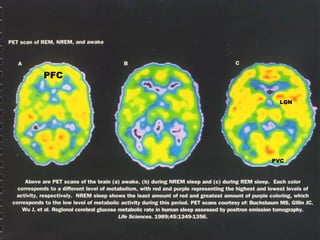

PVC

LGN

PFC